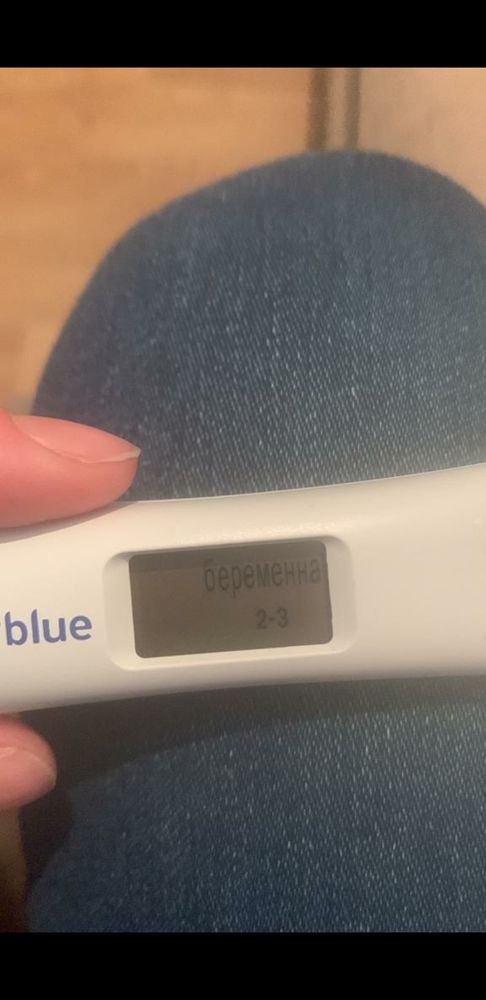

Лимоночка, Получается что этот тест от 11.01.23 показывает верно, просто где-то прочитал что Clear Blue Digital не точно показывает.

Лимоночка, Получается что этот тест от 11.01.23 показывает верно, просто где-то прочитал что Clear Blue Digital не точно показывает.

Gennady Babansky, этот тест показывает результат по уровню хгч, 2-3 недели эмбриональных это 4-5 акушерских как раз. А правильно или нет не знаю, думаю погрешность есть, но в целом наверное верно

Кстати когда она сделала этот тест 11 января, который показал что больше 2ух недель уже, а 13 Января уже в поликлинике врач что-то нащупала рукой в боку у неё она говорила и сказала что ну вот он, что-то такое

А этот 11 января вечером

А этот 11 января вечером

В большинстве случаев все так и говорят что зачатия и тд в декабре было, а начинаешь смотреть учебники, приложения по беременности (каркуляторы и тд) ютуб видео и начинает рисоваться другая картина, что типа вот допустим если бы зачатие было 1го то до 16 января ещё 15 дней грубо говоря, и вот около 5 дней она добирается по трубам, потом крепится и растёт, как пишут 1 мм в день, и так совпадает что увидели 16 января, пя 7,5 мм. Тест на беременность был 11 января клеар блу диджитал показал 2-3 недели, 9 января 2 плоски яркие обычный тест, но оба теста делались вечером, не утром, 13 января врач гинеколог что-то нащупала в боку, типа вот есть там что-то, я понимаю я спрашиваю одно и тоже постоянно у всех и получаю разные но более менее хорошие и обнодежиаающие ответы что это декабрь, спасибо за это людям больше, мне кажется что у меня паранойя уже начинается, я очень сильно хочу чтобы всё было так как Вы пишите что это 25 декабря! В некоторых случаях мне говорили что овуляция могла быть позже и что после овуляции можно забеременеть, вот поэтому наверное переспрашиваю всё, извините если что!

А имеет ли значение в какое время делается тест на беременность утром или вечером, тесты просто делались вечером и вот тот который Clear Blue Digital показал 2-3 недели 11 Января, а знакомая сказала что он реагирует на уровень хгч и что сегодня он может показать 1-2 недели, а типа завтра утром уже 2-3(

Марина, Вот ещё пишут про тест Clear Blue Digital, как Вы считаете может такое быть?

Вот эти тесты один 9 Января вечером, другой 11 января и тоже вечером

Вот эти тесты один 9 Января вечером, другой 11 января и тоже вечером

Понятно вообщем, а Вы не знаете Clear Blue Digital, точно показывают?